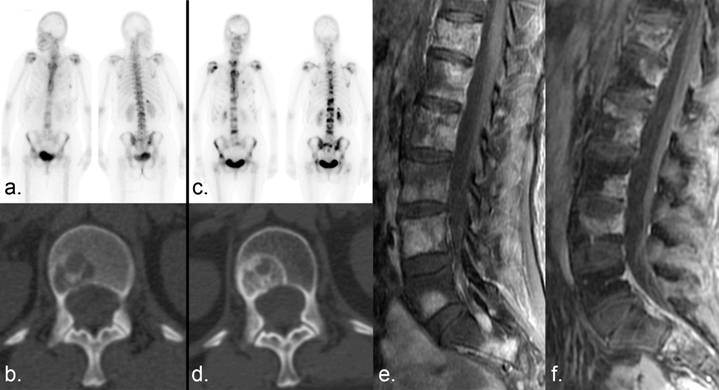

According to the MDA criteria, CR is defined as complete sclerotic fill-in of lytic lesions on radiographs or CT, the restoration of normal bone density on radiography or CT, the disappearance of abnormal tracer uptake on skeletal scintigraphy (SS), and the normalization of signal intensity on MRI (Fig. 4). The PR category includes the development of a sclerotic rim (Fig. 5) or partial (rather than complete) sclerotic fill-in of lytic metastases on radiography or CT; ≥ 50% decrease in the sum of the perpendicular measurements of measurable lesions on radiography, CT, or MRI (Fig. 6); ≥ 50% subjective decrease in the sum of the perpendicular measurements of unmeasurable (ill-defined) lytic or blastic lesions on radiography, CT, or MRI that cannot be accounted for by changes in obliquity or slice placement; and ≥ 50% subjective decrease in tracer uptake on SS (Fig. 7). A caveat to the PR designation involves the osteoblastic flare phenomenon. Interval visualization of sclerotic lesions or lytic lesions with sclerotic rims, in the setting of other signs of PR, does not indicate disease progression but the healing of previously inconspicuous lesions (19). Osteoblastic flare cannot be diagnosed if any preexisting lesions show signs of progression (e.g. enlargement of lytic lesions, development of new lytic lesions) (Fig. 8). PD is defined as ≥ 25% increase in the sum of the perpendicular measurements of any measurable lesion on radiography, CT, or MRI; ≥ 25% subjective increase in the size of unmeasurable (ill-defined) lytic or blastic lesions on XR, CT or MRI that cannot be accounted for by obliquity or slice placement; ≥ 25% subjective increase in tracer uptake on SS; or the development of new metastases. An increase in tracer uptake on SS may need correlation with other imaging studies to exclude the scintigraphic flare phenomenon, which is typically seen within the first 3 months after therapy. Scintigraphic flare occurs when healing sclerosis results in more tracer uptake than was caused by the untreated lesion (Fig. 9) (20-24). SD is defined as < 25% increase or < 50% decrease in size or no change in measurable lesions and no new lesions.

Figure 9

Scintigraphic flare. (a) Numerous bone metastases show tracer uptake on a Tc 99m MDP bone scan in a patient with breast cancer. (b) Companion CT examination demonstrates a lytic metastasis in the L1 vertebral body. (c) Six months later, the lesions demonstrate increased tracer uptake. (d) Companion CT shows sclerotic fill-in of the lytic lesion, which can occur with disease progression or healing. (e, f) Fat-saturated T1-weighted sagittal MRI examinations of the lumbar spine obtained (e) 1 month and (f) 2 months after the bone scans show a decrease in the size and/or enhancement of the metastases, indicating a positive response to therapy. Incidental note is made of interval insufficiency fracture of the superior endplate of L4 on (f). The increased MDP uptake on the bone scan (b) was the result of healing sclerosis and representative of a scintigraphic flare in a patient undergoing partial response rather than progressive disease.